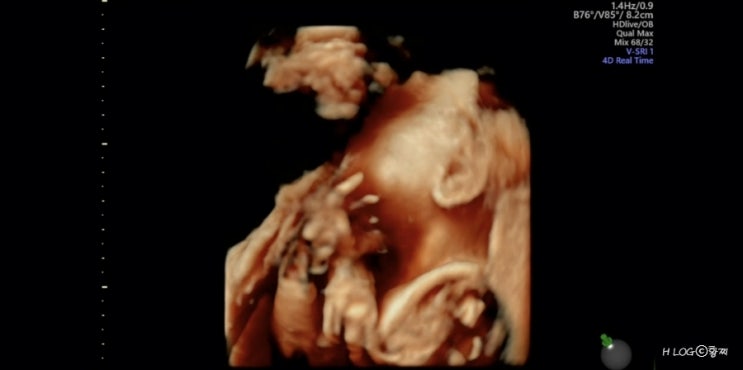

[임신 24, 25주] 임당검사, 입체초음파

내가 벌써 7갤이라니.. 시간 너무 빠르다? 출산하기전에 빨리 놀아야되는데 잘 놀기보다 잘 먹는중 ㅋㅋ...